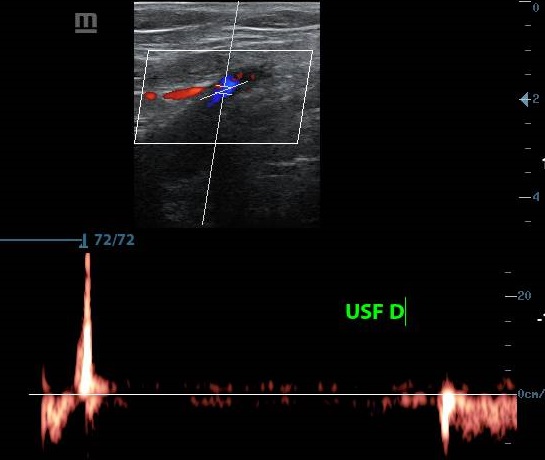

ECODOPPLER

El Eco Doppler es un tipo de ultrasonido que estudia el flujo de sangre que se transporta por las arterias y venas; es decir, permite conocer la cantidad, velocidad y consistencia del flujo sanguíneo en un momento concreto.

• Doppler Arterias renales